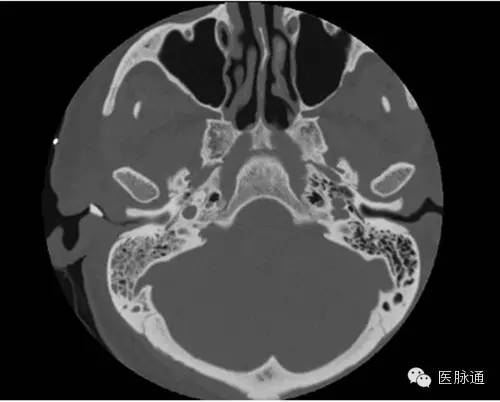

事故一: 医生诊断女孩为霉菌性外耳道炎,因为不确定菌种,还需要进行分泌物培养,再对症下药。 事故二: 杭州60岁一大爷也遇到了耳朵长毛的情况。章大爷前一天自己掏完耳朵,第二天耳朵就痛痒难忍,前来就医。 霉菌性外耳道炎和吴先生的脚气进耳朵是一个道理,都是真菌感染,只不过致病菌可能会不同。脚气的病菌多为红色毛癣菌、石膏样毛癣菌、絮状表皮癣菌、犬小孢子菌、石膏样小孢子菌、白色念珠菌......而耳朵的致病菌多为以曲霉菌、念珠菌、青霉菌及毛霉菌。 不过相同的是,这些菌都可能因为工具而带入耳朵,并在耳朵里落地生根...... 根据不同真菌种类,耳朵长出的“毛”颜色也会不一样。 曲霉菌、青霉菌感染,菌落的“毛”会是绿色的。 念珠菌、毛霉菌感染,“毛”会是白色的,程度轻的能看到一些霉丝和霉点,严重的可能会有一些脓性分泌物。 还有黑色的“毛”。不过这可能不是单一感染了某种真菌,还可能是:耳屎堵在耳朵里时间太长,让它在外耳道内潴留局部发生氧化了;陈年血痂被抠了出来;感染了黑色真菌后的团块;黑色素瘤之类的疾病(不过一般抠出来的会是黑色新生物,大多数伴有疼痛和出血)。 其实真菌进耳朵,在多数情况下都可以避免。 比如减少掏耳朵的次数。“耳屎”耵聍是保护着我们的耳朵的,它呈弱酸性的,有抑制真菌生长的作用,如果频繁掏耳朵,将耳道清理得过分干净,就会使耳道失去一层保护屏障。 用一次性采耳工具,减少交叉感染的可能。耳道也有着自己的微生物环境,当表皮葡萄球菌和棒状杆菌占多数时,耳道会更健康。如果霉菌进入耳道,菌落的平衡破坏,耳道就会真菌感染。 表皮葡萄球菌正常存在于人的皮肤、鼻腔及肠道中 棒状杆菌 如果实在觉得耳朵被“堵”住了,难受得不得不掏,又不敢自己掏,可以挂耳鼻喉科,让医生来一波专业操作! 02 硬核异物篇 玩具零件、泥土、木块金属块......总有些硬核异物在不断突破耳朵的感受。 事故三: 24岁的于先生掏因为耳朵掏不动而到医院检查,医生发现他的耳道里竟然有个算盘珠! 回溯起来,原来这颗算盘珠是他自己10岁的时候塞进耳朵的,因为当时怕被家长骂就没说而不了了之,于是这颗珠子就在于先生的耳朵里安安静静地躺了14年。 事故四: 重庆市民彭女士在给六岁的儿子豪豪掏耳朵时,发现他的耳朵里好像有异物,于是便把他送到医院检查。 医生在豪豪耳朵里取出了一棵植物种子,并且已经发芽! 医生表示,耳道里的温度是37度左右,再加上比较湿润,是适合种子生长、发芽的,这种情况如果再晚些就医,很可能会对孩子的听力造成损伤。 事故五: 以及这位心大患者,用金属硬物抠耳朵,但是金属却塞到耳道深处拿不出来了。 左方耳道亮光为金属异物,图片来自医脉通 耳道是用来传递声波的,有着一定的长度和宽度,大概长度2.5-3.5cm,粗0.7cm 左右,别看小小的几厘米,却有可能因为它弯曲的形状而藏住小东西! 成人的耳道走形略成“S”,先向前上弯曲,然后向后下,再向前下 不过为了避免进异物,耳朵也有着对策。耳道内的皮肤上分布着毛囊和耵聍腺,耵聍腺会分泌一定量的耳屎来粘附灰尘和进入的外物,耳朵里的小绒毛也会阻挡异物进入。 其实耳朵在一般情况下并不容易进入异物,如果进了东西,多数当时就会感到疼痛。 但因为每个人的外耳道长度不一样,进了东西后感受也可能不同,有的人会有异物感、阻塞感、听力改变等症状,也有的人当时感觉不到异常。 所以,蝌蚪君叮嘱一句,如遇耳朵进了异物又拿不出来,一定要及时去医院,免得自己的胡乱操作损伤了听力! 03 恐怖爬虫篇 事故六: 大连市中心医院接诊了一位60多岁的男性老人,他在前一晚睡觉时感觉耳朵里面不舒服,但没在意,第二天醒来耳朵里就像敲鼓一样。 医生检查后发现老人的耳道被一层白雾一样的絮状物封闭了,像网一样的这层絮状物背后,一个类似虫子的活物在不断地动。 原来是进入耳道的蜘蛛已经在里面结了网! 医生用专用的耳道清洗器向老人的耳道内注水清洗,一只绿豆大小的蜘蛛才被冲洗了出来。 想要避免自己碰到样的恐怖情况,最有效的办法就是保持家中卫生干净,多做蚊虫的消杀。尤其在家里经常见到小飞虫、瓢虫、蚰蜒(俗称草鞋底)、小蟑螂,需要格外保持警惕,这些虫子尤其喜欢温暖潮湿的人类耳朵! 但是如果真的遭遇虫子进耳道,千万别用土办法解决,比如滴香油、食用油、醋,还有用手电筒照亮,吸引虫子…… 这样不仅不科学,还容易造成耳道感染,让耳道内的情况更加复杂,给治疗带来难度。 04 悲伤事故篇 虽然“做完手术落下了纱布”这种传说级的事故,在普通外科手术上鲜有发生(每一场外科手术都会清点医疗用品数量),但在耳朵手术里发生的概率的确会比普通手术更高。 耳科病人做完手术后,进行术后调理和康复时一般会给病人耳部覆盖上无菌纱布,用来包扎敷料、消毒或保护手术部位,这也给将纱布、棉花误留创造了机会。 不过随着医疗水平的提高,这种小概率事件以及极少发生了,大家不必过度担忧。 05 避免耳朵生长奇怪的东西 要养成正确的卫生习惯 很多人比较享受掏耳朵的过程,前往采耳店、足疗店、按摩店掏耳朵,觉得掏完身心轻松,非常解压。 但是顾客们都同用一套工具,万一遇到消毒不到位的情况,采耳就变成了“真菌杂烩”,如同足疗传染脚气,采耳也容易将上一个客人的“耳气”带回家。 当然,也别矫枉过正,用耳毛来挡住异物(一般人做不到)。 世界上最长的耳毛50公分,其实他是患了“传男不传女”的人类外耳道多毛症 如果真的感觉自己的耳屎太多,有种堵了东西的感觉,甚至了影响听力,在医学上这种情况叫做耵聍栓塞。可以前往正规医院耳鼻喉科挂号,医生将会用药水、无影灯、内窥镜等工具进行安全可靠的“掏耳屎”(据说掏过的人在看到“成果”时都非常的爽),蝌蚪君也想尝试一二! 你耳朵曾经进过东西吗?你有听闻过身边朋友耳朵进过奇葩东西吗?他们都是怎样处理的呢?快在评论处告诉蝌蚪君吧! 审核专家:袁先道,首都医科大学北京安贞医院耳鼻喉科副主任医师,医学博士。 来源:蝌蚪五线谱